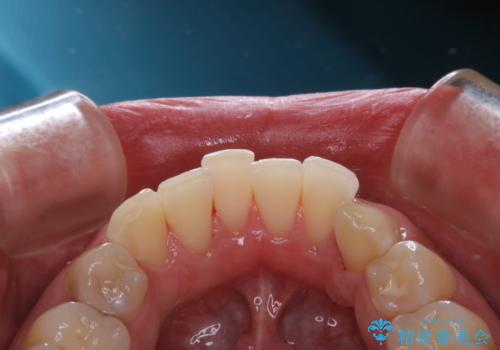

- 歯磨きをしても取れない汚れが気になるとのことで来院されました。PMTC60分コースを行いました。

歯周病やむし歯にならないように、定期的にプロフェッショナルケアを受け、お口の清潔を保つことが大切です。